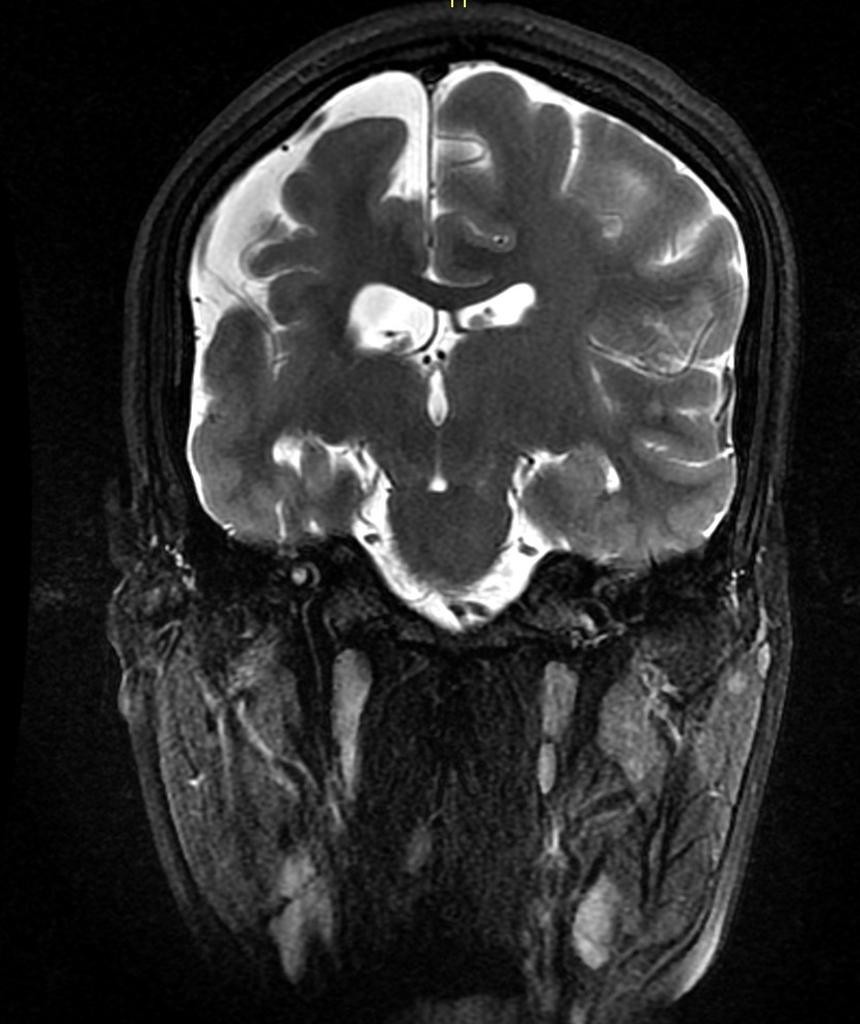

Sclérose hippocampique

• Sclérose de la corne d’Ammon =  sclérose temporale mésiale

• Sémiologie

• Perte des digitations de la tête de l’hippocampe (seul signe au début)

• Atrophie (perte hauteur)

• Gliose (hyper T2/FLAIR)

• +/- Atrophie du Gyrus ParaHippocampique (GPH)

• +/- Atteinte du pole temporal avec HS (ne modifie pas le pronostic post-op)

• +/- Atrophie fornix et corps mamillaire du côté atteinte (atteinte associée du système limbique)

• +/- Dilatation réactionnelle corne temporale